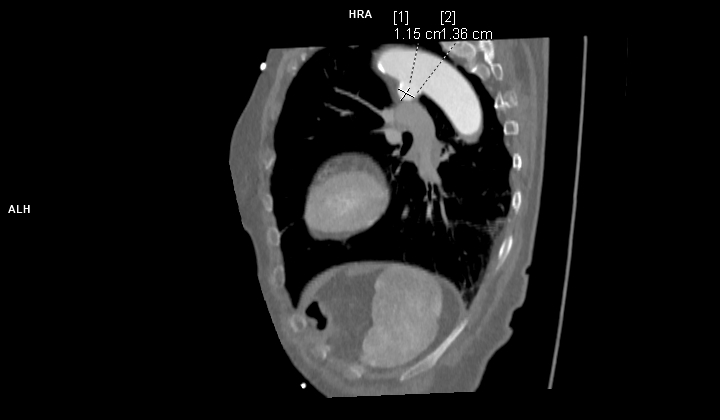

Figurile 1 si 2: reconstrucție multiplanară din achiziție angio în timp arterial – aorta toracică

Discuţie caz nr 102: Ductul arterial este o structura de by-pass între aorta descendentă și trunchiul de arteră pulmonară care funcționează în viață intrauterină deoarece plămânii nu sunt aerați; în mod normal se închide în primele zile după naștere. Imaginile prezentate arată că ductul arterial este închis însă se evidențiază creșterea calibrului unei reminiscențe a ductului arterial la deschiderea în aorta descendentă.

DE LUAT ACASĂ!!! Inserția ductului arterial în aorta descendentă toracică este util să fie cunoscută deoarece dacă avem canal arterial permeabil acesta poate fi de dimensiuni mici și poate să nu cauzeze probleme semnificative rămânând nedetectat – practic descoperire întâmplătoare.